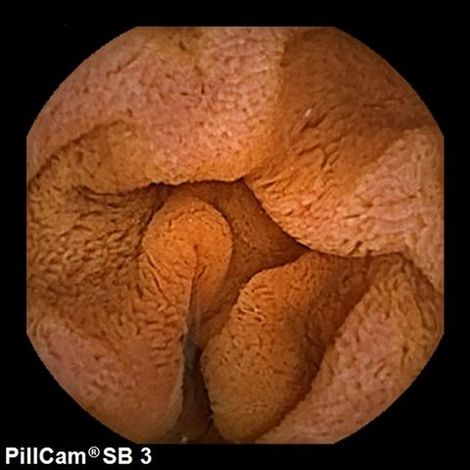

Durch eine Kapselendoskopie mit der PillCam® SB Videokapsel kann Ihr Dünndarm genau untersucht werden. Sie erhalten hierzu von uns eine Videokapsel, die Sie anschließend schlucken. Die Videokapsel verfügt über eine Kamera und Lichtquellen. Sie wandert langsam durch Ihren Körper und sendet dabei Bilder an einen Datenrekorder, den Sie an der Taille tragen. Anschließend kann Ihr Arzt die Bilder mittels einer speziellen Software am Computerbildschirm auswerten. Während der Untersuchung, die bis zu zehn Stunden dauern kann, können Sie sich frei bewegen.

Ein vollständig sauberer Dünndarm ist notwendig, um optimale Bilder für eine erfolgreiche Untersuchung zu bekommen. Vor der Untersuchung erhalten Sie deshalb genaue Hinweise zur Darmvorbereitung. Bitte informieren Sie uns im Voraus über alle Medikamente, die Sie einnehmen, da deren Dosierung für die Untersuchung möglicherweise verändert werden muss. Informieren Sie uns auch darüber, ob Sie einen Herzschrittmacher oder andere elektromedizinische Geräte implantiert haben, sowie über erfolgte Operationen im Bauchraum, Schluckbeschwerden oder bekannte Verengungen im Magen-Darm-Trakt.

Zur Vorbereitung auf die Untersuchung befestigen wir zunächst ein Sensorenfeld mit Hilfe von Klebehüllen auf Ihrem Bauch. Anschließend wird die Videokapsel mit Wasser geschluckt und passiert so den Verdauungstrakt auf natürliche Weise. Dabei überträgt sie Videobilder an einen Datenrekorder, den Sie eng an der Taille mit sich führen. Vier Stunden nach dem Schlucken der Kapsel dürfen Sie normalerweise wieder essen. Etwa acht Stunden nach dem Schlucken der Kapsel ist die Untersuchung beendet.

Am Ende der Untersuchung werden der Datenrekorder und das Sensorenfeld wieder entfernt. Die während der Untersuchung aufgenommenen Bilder werden anschließend auf einen Computer übertragen, auf dem der Arzt sie betrachten kann. Nach Einnahme der Kapsel bis zu ihrer Ausscheidung sollten Sie sich keiner medizinischen Untersuchung mit einem Magnetresonanztomographen (MRT) unterziehen und sich nicht in der Nähe eines MRT-Gerätes aufhalten.